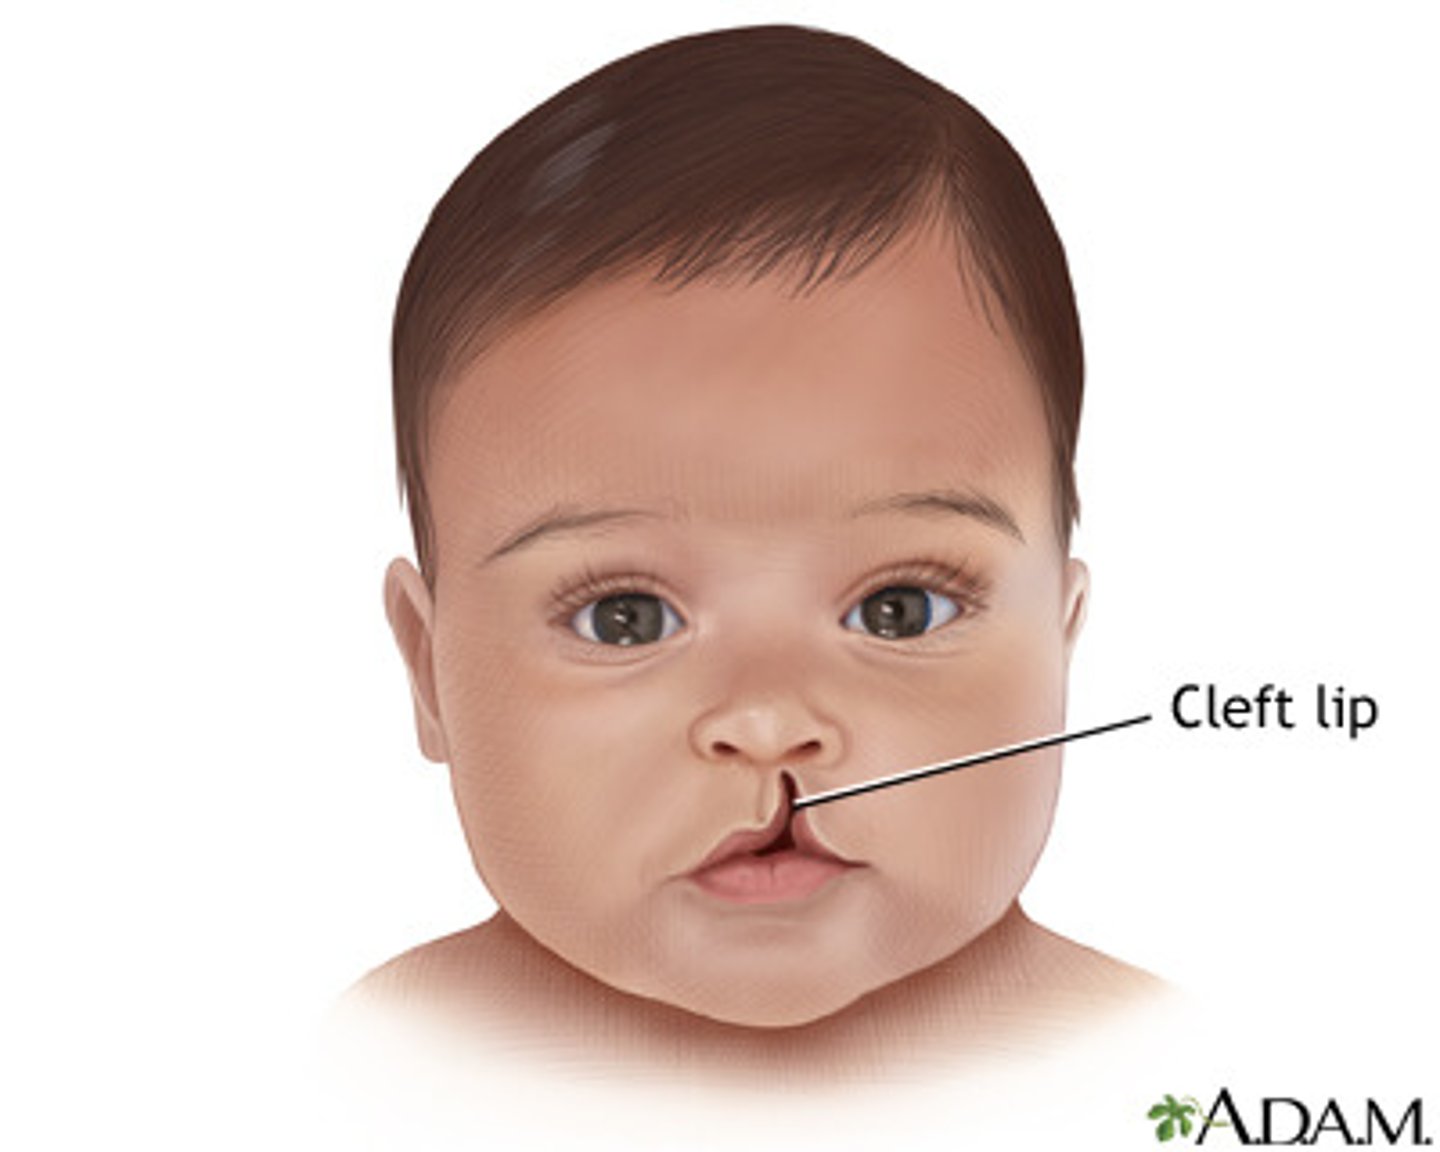

Cleft lip is defection fusion of the ____ and _____

medial nasal process

maxillary process